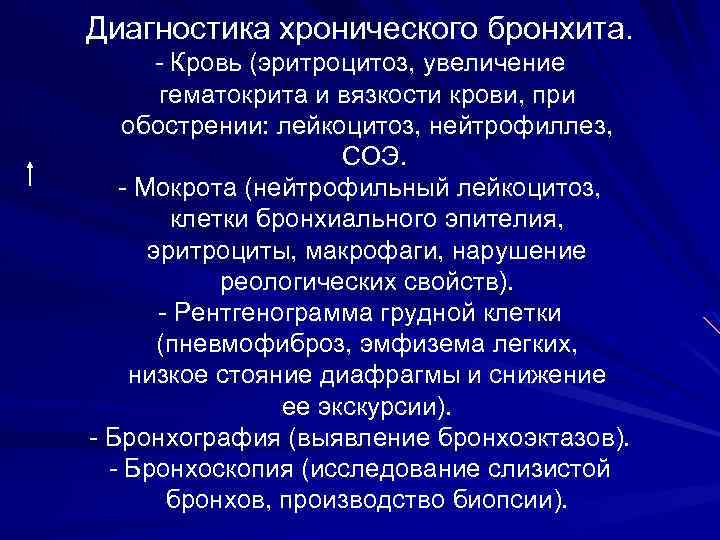

Диагностика хронического бронхита. - Кровь (эритроцитоз, увеличение гематокрита и вязкости крови, при обострении: лейкоцитоз, нейтрофиллез, СОЭ. - Мокрота (нейтрофильный лейкоцитоз, клетки бронхиального эпителия, эритроциты, макрофаги, нарушение реологических свойств). - Рентгенограмма грудной клетки (пневмофиброз, эмфизема легких, низкое стояние диафрагмы и снижение ее экскурсии). - Бронхография (выявление бронхоэктазов). - Бронхоскопия (исследование слизистой бронхов, производство биопсии).